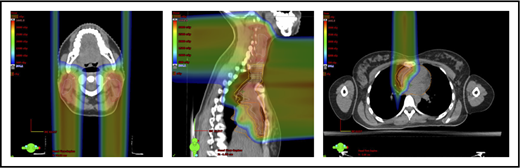

Motion management

A 4D CT scan can help to establish the extent of respiration-induced anatomic motion and the appropriate ITV expansion. However, this introduces an additional uncertainty; to mitigate the latter, the radiation volume has to be increased. Thus, use of DIBH is ideal to reduce the motion of the mediastinum and its respiration-dependent change in shape (thinner during inspiration, wider during free breathing) (Figure 7).59 It is accomplished by acquisition of the anatomical data in a fixed respiratory phase. DIBH can have the additional benefit of displacing the heart inferiorly, as well as expanding the lungs away from the target, potentially reducing the dose received by these OARs.

Use of DIBH can help to manage some of the uncertainties associated with the use of proton therapy. Compared with free breathing (right panel), DIBH expands the lungs, moves the heart downward, and causes the mediastinum to become thinner (left panel).

DIBH can be accomplished in several ways, such as by actively blocking airflow, voluntary breath holding, or synchronization (respiratory gating). Each of these methods has advantages and limitations when used with proton therapy, particularly PBSPT, which tends to have longer “beam-on” time than PSPT. Interfractional reproducibility of the diaphragm position during the course of the radiation fraction should be evaluated.60,61 Regardless of the breath-hold technique used, on-board imaging can be useful to verify and check the daily reproducibility of the lung volume against that in the treatment-planning CT.